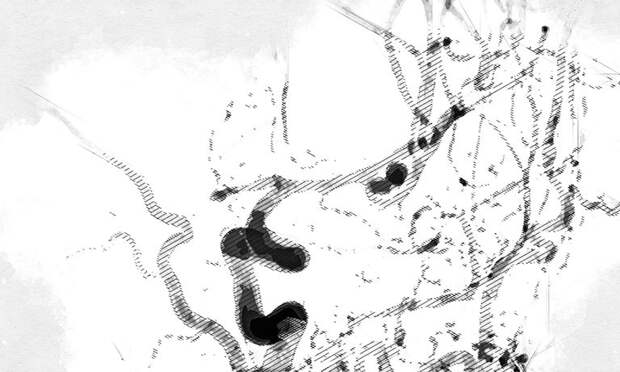

При обследовании у орловца выявлена мешотчатая аневризма со сложной анатомией и несколькими полостями в средней мозговой артерии.

Орловские врачи экстренно провели консилиум с ведущими нейрохирургами.У пациента был высок риск повторного разрыва аневризмы, что могло привести к смерти. Врачи приняли решение выполнить высокотехнологичную операцию – эмболизацию аневризмы с помощью микроспиралей.